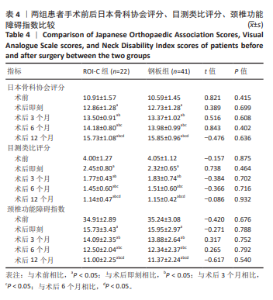

2.6 手术前后影像学评估 两组患者术后C2-7 Cobb角、T1倾斜角,椎间隙高度均较术前显著改善,两组组内不同时间点的C2-7 Cobb角、T1倾斜角,椎间隙高度比较存在显著差异(P < 0.001),而不同分组之间的评分差异无显著性意义(P > 0.05),并且两组在不同时间点的趋势也无显著差异(P > 0.05)。 ROI-C组术后即刻、术后3,6,12个月的C2-7 Cobb角、手术节段椎间隙高度及术后3,6个月的T1倾斜角较术前均显著增加;术后3,6,12个月的C2-7 Cobb角、术后3个月的T1倾斜角均较术后即刻明显增加;术后6个月的C2-7 Cobb角较术后3个月明显增加,差异有显著性意义(P < 0.05)。钢板组术后即刻、术后3,6,12个月的C2-7 Cobb角、手术节段椎间隙高度及术后即刻、术后3,6个月的T1倾斜角均较术前明显增加;与术后即刻相比,钢板组术后3,6,12个月的C2-7 Cobb角及术后3,6个月的T1倾斜角均明显增加;术后6个月的C2-7 Cobb角较术后3个月明显增加,术后12个月的T1倾斜角较术后3个月明显减小;术后12个月的T1倾斜角较术后6个月明显减小,差异有显著性意义(P < 0.05)。见表5。"